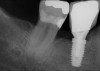

Fig 15. (Case 3) Radiograph of tooth No. 19, which had a hopeless prognosis.

Figure 15

Fig 16. Radiograph of extraction socket. Buccal and lingual plates were defective.

Figure 16